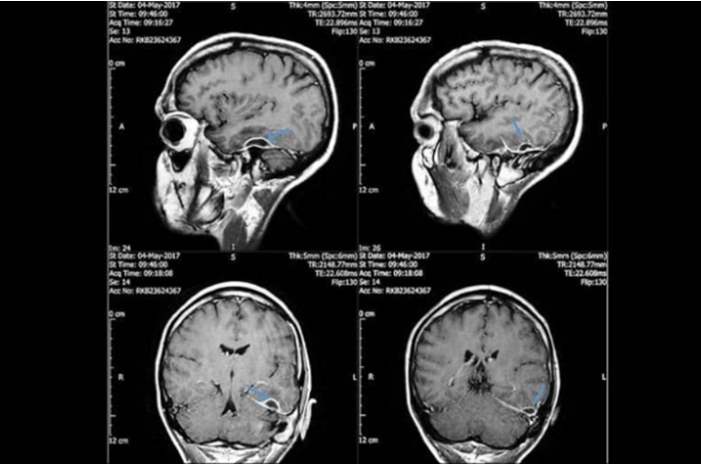

ففي المستشفى، اكتشف الأطباء أن المشكلة "باتت" أعمق مما كان يعتقد وأنها توجد داخل جمجمته.

وبحسب الأطباء فإن الالتهاب أصاب الخلايا داخل الجمجمة، ولم يصل إلى خلايا الدماغ.